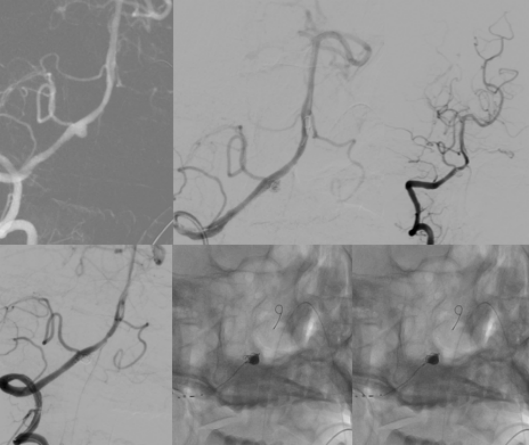

脑血管病介入团队立即启动绿色通道

检查发现

“元凶”是大脑椎动脉上

一个形状不规则的“小气球”

——医学上称为“夹层动脉瘤”

它破裂了

医生从他大腿根部的血管

插入一根细小的导管

一路“导航”到大脑深处的病变位置

然后放入一个特殊的

网状支架和数枚柔软的铂金弹簧圈

就像精准地堵住水管上破裂的鼓包

同时用网格加固水管壁

被称为

血流导向装置植入+弹簧圈栓塞术

脑血管造影(DSA):这是确诊并锁定动脉瘤的“金标准”。医生通过它能看到脑血管的清晰三维结构,明确“炸弹”的位置和形态,为手术铺路。

血管内介入治疗(栓塞术):

从大腿血管“打隧道”进去,用弹簧圈填塞动脉瘤,或用支架辅助封堵。这是目前的主流微创治疗方法。